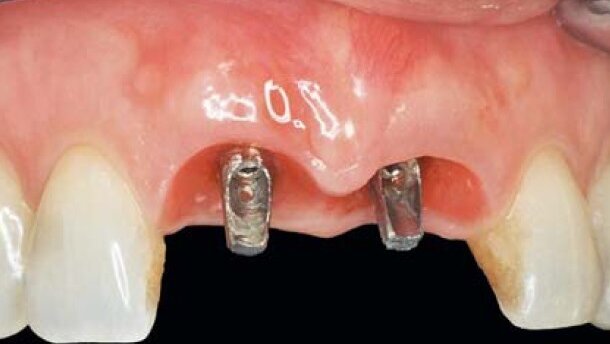

Niedawno przeprowadzone badanie wykazało, że biowchłanialne membrany osłonowe i białka pochodne matrycy szkliwa (EMD) przyspieszają gojenie po natychmiastowym wszczepieniu implantów przezśluzówkowych w zębodoły po ekstrakcji. Grupa membran biowchłanialnych uzyskała jednak lepsze wyniki w porównaniu do grupy EMD pod względem zarówno przylegania, jak i umiejscowienia tkanki miękkiej wokół implantu, poprawiając gojenie tkanek twardych i miękkich, szczególnie w obszarach o wysokich wymaganiach estetycznych (Ryc. 1 i 2).

W przypadku połączeń implantu z filarem, gdy występuje mikroprzestrzeń, przenikanie drobnoustrojów może powodować stan zapalny i zanikanie krawędzi kości. Dlatego tak ważne jest ograniczanie do minimum obecności bakterii w obszarze filaru z implantem. Wykazano, że uszczelnienie zapewniane przez filar o zwężonym kształcie blokującym, jest hermetyczne w stosunku do inwazji bakteryjnej in vitro. 2 tygodnie po zabiegu chirurgicznym remodelowanie koron tymczasowych i podścielenie samopolimeryzującym akrylem powinno wywrzeć minimalny nacisk na krawędź policzkową, optymalny na sąsiadującą brodawkę i powstanie wierzchołków przy sąsiadujących powierzchniach stycznych (Ryc. 3-6). Koncepcja nacisku na szyjkę działa jedynie w płaszczyźnie proksymalnej, a nie twarzowej, gdzie tkankę miękką i skupiska kolagenu należy rozciągać lub ściskać, by stymulować brodawkę.